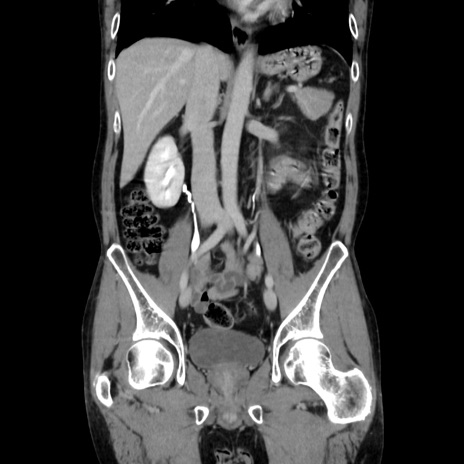

症例37(冠状断像)

【症例】40歳代 男性

【主訴】腹痛

【現病歴】4時間ほど前に電車に乗車中に臍部上より腹痛出現。徐々に増悪し起立困難となり、救急外来受診。生ものは数日食べていない。今朝お雑煮を食べた。

【身体所見】BT 36.8℃、BP 117/84mmHg、HR 91/min、SpO2 97%、苦悶様、腹部:臍上部広範囲圧痛あり、反跳痛±

【データ】WBC 8100、CRP 0.03